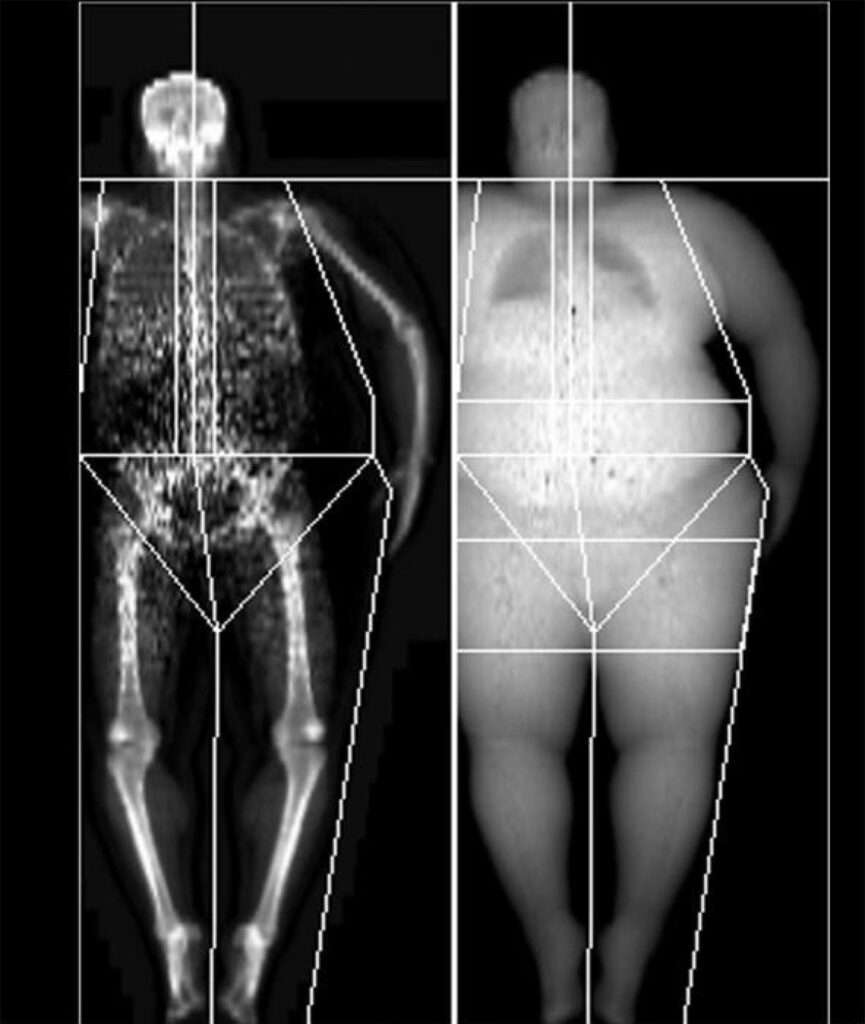

La absorciometría dual de rayos X, conocida como DXA (por sus siglas en inglés), es una técnica de imagen que permite medir con precisión la densidad mineral ósea, especialmente en el hueso cortical. Esta densidad se expresa típicamente en gramos por centímetro cuadrado (g/cm²), una unidad que representa la cantidad de mineral óseo presente en un área específica del hueso. Cabe destacar que existen rangos normales distintos para cada hueso del cuerpo, así como para cada tipo de equipo DXA, debido a variaciones técnicas entre las diferentes máquinas utilizadas en la práctica clínica.